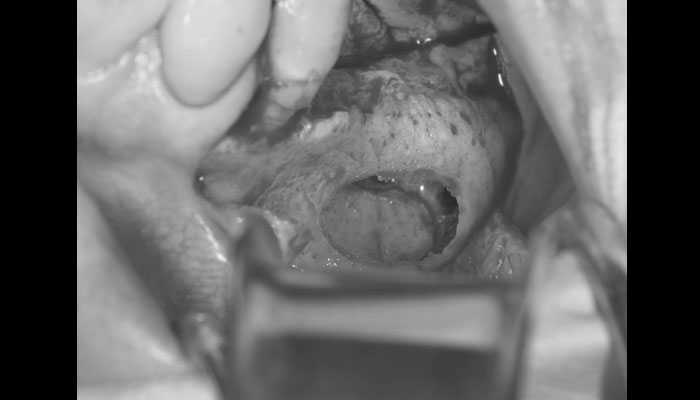

4.サイナスリフト

ピエゾサージェリーという機材を使用して、安全に上顎洞の側壁を開窓し、上顎洞粘膜(シュナイダー膜)を挙上します。

インプラントを入れるドリルホールを開け、骨の厚みを増やすために使用する骨補填材の「Bio-oss」を詰めます。

6.サイナスリフト・インプラント埋入

サイナスリフトと同時に2本のインプラントを埋入しました。

このような手術が歯茎の切開から縫合まで約30分程度で終了します。 -